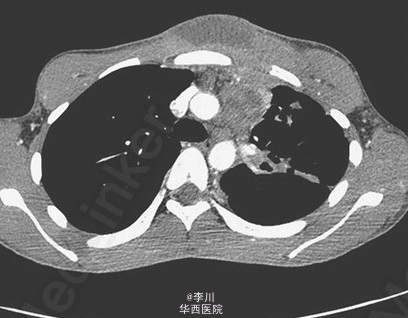

18 岁,男性,既往体健,主因咳嗽 3 月余入院,伴咳淡红色痰、体重下降和发热。近几周其前胸壁出现进展性、局灶性红肿。痰涂片结果为抗酸性染色菌,痰培养结果提示为结核分枝杆菌。HIV 试验呈阴性。患者接受标准抗结核杆菌治疗 8 周,感染仍未控制,表现为红肿加重、皮肤斑疹和皮下脓肿波动。立即给予脓肿切开引流术。逐渐痊愈。Troelsen T, Hilberg O. 2014. Images in clinical medicine. Tuberculous abscess. N Engl J Med. 371(2): 161.